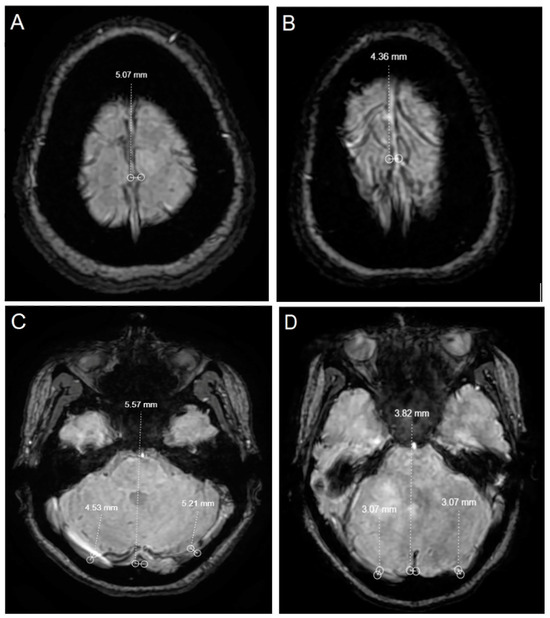

| SSS | 5.4 ± 0.9 | 4.8 ± 0.6 | 5.9 ± 0.8 | <0.001 | <0.001 |

| Sinus rectus | 4.6 ± 0.8 | 4 ± 0.7 | 5 ± 0.5 | <0.001 | <0.001 |

| Right transverse sinus | 5.2 ± 1.6 | 4.8 ± 1.4 | 5.5 ± 1.7 | 0.020 | 0.015 |

| Left transverse sinus | 4.1 ± 1.6 | 3.7 ± 1.4 | 4.4 ± 1.7 | 0.005 | 0.003 |